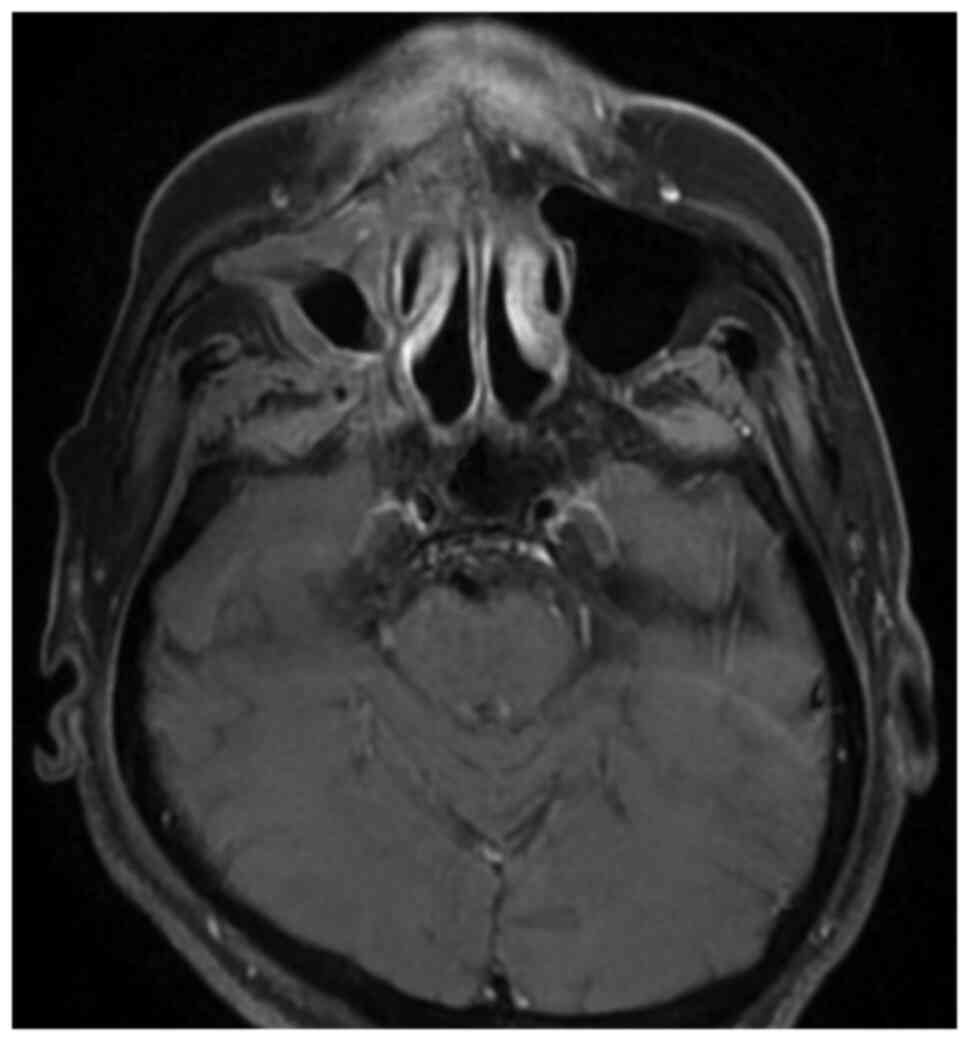

Regression of advanced maxillary sinus cancer with orbital invasion by combined chemotherapy and immunotherapy: A one‑year follow‑up case report

A case of advanced maxillary cancer undergoing a combination of chemotherapy and immunotherapy is reported. The subject a 59‑year‑old man had a history of nasopharyngeal carcinoma treated with concurrent chemoradiotherapy in 2004. The patient was diagnosed with a right maxillary sinus carcinoma invading the right orbital fossa (cT4aN0M0, stage IVA) in 2019. Computed tomography revealed soft tissue swelling involving the right maxillary sinus, right nasal cavity, inferior extraconal space of the right eye, right cheek and right hard palate with extension into the right pterygopalatine fossa. The patient refused surgery and radiotherapy but accepted chemotherapy in combination with immunotherapy. A marked regression of advanced maxillary sinus cancer with orbital invasion using this regimen was noted in the one‑year follow‑up period. A literature review on treatment for advanced maxillary sinus cancer was also conducted and the results revealed that this combination regimen may play a role in the treatment of advanced maxillary sinus cancer but further investigation is required to determine the effect of combination of chemotherapy and immunotherapy on advanced maxillary sinus cancer.